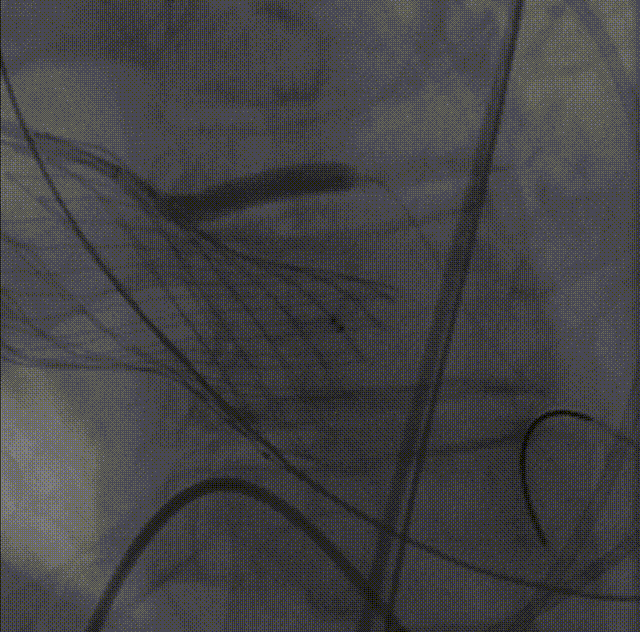

26VenusAplus+snare